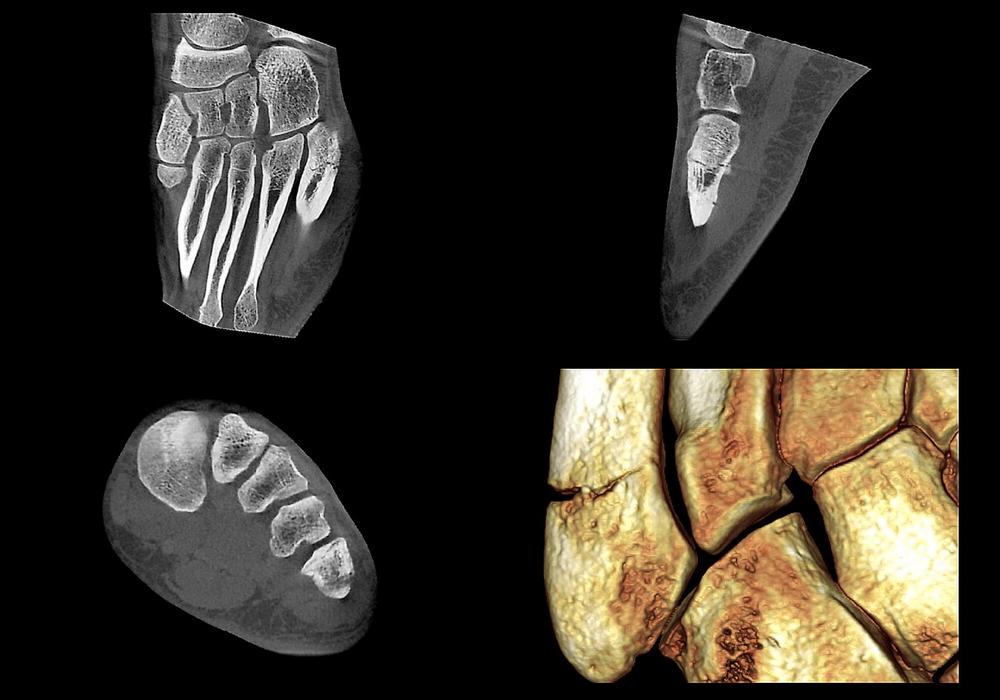

Das breite Anwendungsspektrum der digitalen Volumentomographie (DVT) in der O&U ergibt sich aus der hochauflösenden und strahlungsarmen Bildgebung sowie aus der einfachen Anwendung am Patienten. So hat sich die 3-D-Schnittbildgebung mit dem digitalen Volumentomographen SCS MedSeries® H22 auch im Bereich der Extremitätendiagnostik bei Kindern und Jugendlichen etabliert. Im Hinblick auf die Wahl eines geeigneten Diagnostikverfahrens […]